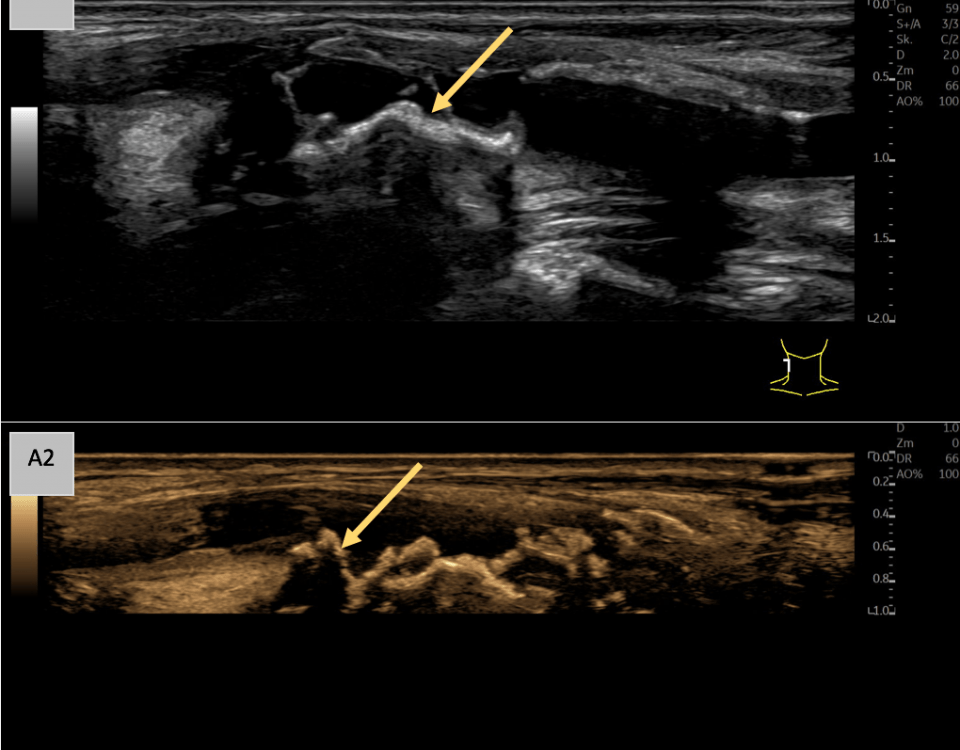

Preoperative ultrasonographic findings showed an oval hypoechoic inhomogeneous mass, approximately 4 x 3 x 1.5 cm in levels III to IV of the left side of the neck below the sternocleidomastoid muscle. (Fig. 1) The mass was partly indistinct to the adjacent tissue and demonstrated peripheral perfusion with no central vascularity. (Fig. 2) The surrounding soft tissues appeared oedematous and thickened. (Fig. 1 – 2)

Figure 1. Hypoechoic inhomogeneous mass partly indistinct from the adjacent tissue in Levels III to IV of the left neck; ACC = Common carotid artery; MSCM = sternocleidomastoid muscle.